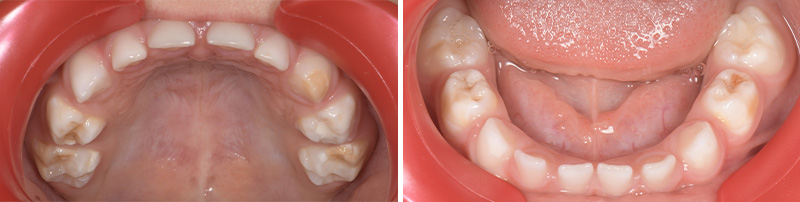

Fig. 03 : arcades maxillaire et mandibulaire d’un enfant atteint de HSPM.

Un enfant présentant une HSPM a 5 fois plus de risques de présenter également une MIH en denture permanente.